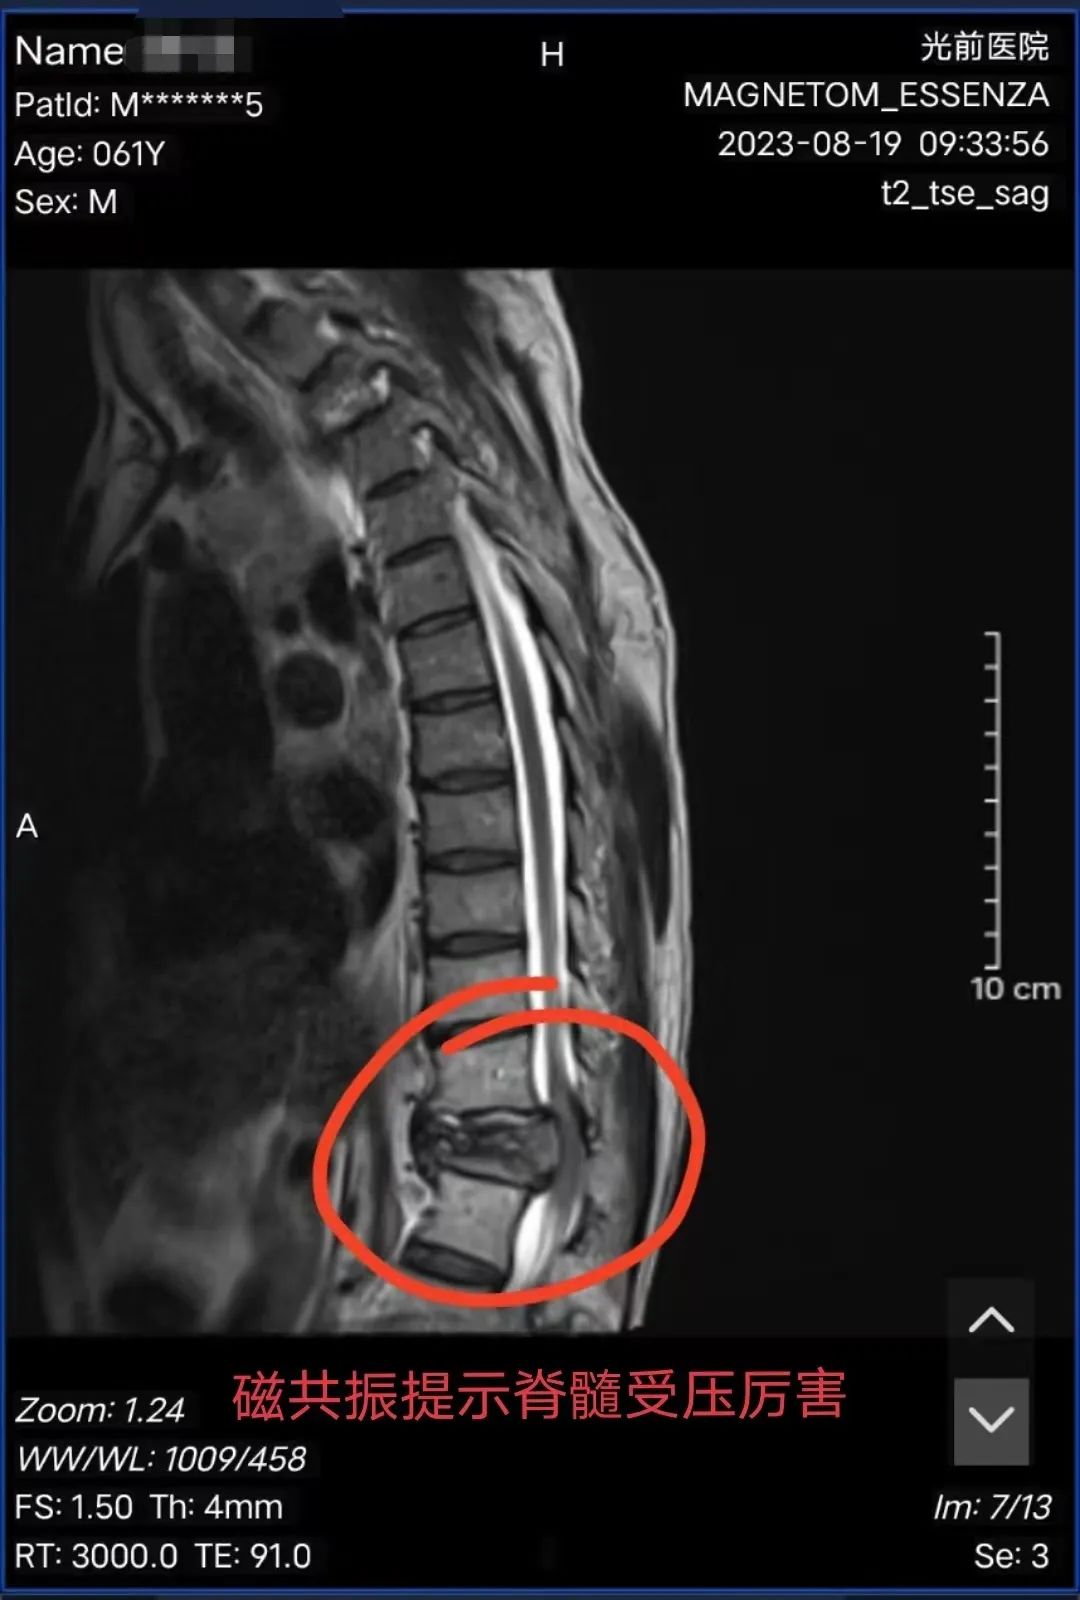

患者陳阿伯,永春人,以“確診右肺癌1年并治療后,腰痛伴左下肢乏力2天”為主訴入住我院腫瘤放療三區(qū),入院后完善MRI提示“胸12椎體病理性骨折并椎管狹窄,脊髓損傷”,經(jīng)骨科詹志強(qiáng)主治醫(yī)師會(huì)診后,考慮陳阿伯為急性胸12椎體病理性骨折并不全癱瘓,且癱瘓程度呈進(jìn)行性加劇趨勢。既往已有轉(zhuǎn)移病灶放療病史,再次給予保守治療,效果不佳,脊柱穩(wěn)定會(huì)繼續(xù)加重,陳阿伯將面臨完全癱瘓的困境,與陳阿伯及家屬溝通后,告知符合手術(shù)指征,陳阿伯及家屬表示相信我院骨科技術(shù)水平,決定手術(shù)治療。

黃進(jìn)福主任帶領(lǐng)骨科團(tuán)隊(duì),結(jié)合陳阿伯腫瘤病灶侵犯的情況,對其病情進(jìn)行認(rèn)真研究,陳阿伯左下肢肌力0級,右下肢肌力2級,肛門括約肌反射差,決定行“后外側(cè)入路下胸12椎體部分切除+鈦網(wǎng)植入+骨水泥填塞+椎弓根釘內(nèi)固定術(shù)”。

▲手術(shù)前后影像對比